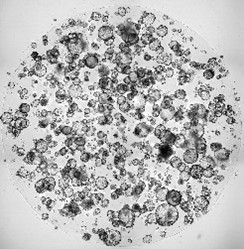

- Des modèles expérimentaux innovants (dont les modèles d’organoïdes tumoraux)

Développement de tests fonctionnels personnalisés

Nous développons des tests ex vivo sur des organoïdes dérivés de tumeurs de patientes, consistant à exposer ces modèles à différents traitements (médicaments, radiothérapie) afin d’évaluer leur efficacité à l’aide par exemple de tests biochimiques évaluant leur viabilité, de tests clonogéniques ou du test RECAP (évaluation de leurs capacités de réparation de l’ADN).

Un enjeu clé est la miniaturisation et la rapidité de ces tests, afin de les intégrer dans la pratique clinique, notamment en situation de récidive.

- Organoïdes dérivés de tumeurs